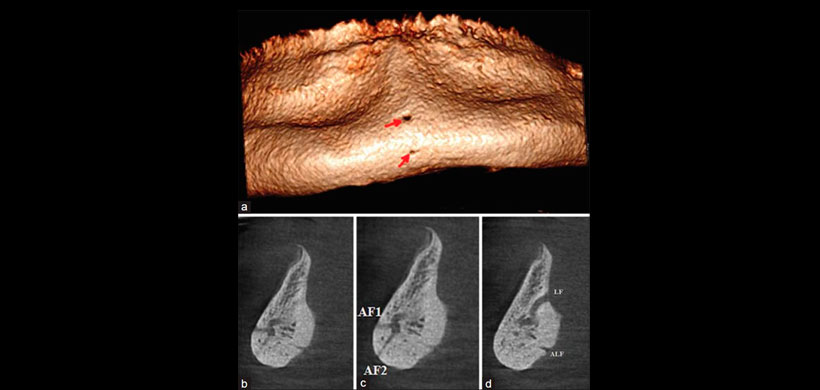

Figura 1: Vista frontal de la emergencia bucal del nervio incisivo en la mandíbula de la línea media (flechas),

(b-d) comunicaciones de los conductos de salida bucal y lingual (foramen lingual) del nervio incisivo y reconstrucción de tres cortes transversales continuos.

El presente caso es de un paciente de 60 años en sínfisis mental desde el lado lingual, el cual reveló dos LF con dos aperturas adicionales (Figura 1). Uno de ellos estaba ubicado en el lado bucal y el otro en el borde inferior de la sínfisis. El historial dental fue significativo para la periodontitis avanzada y la pérdida ósea severa, y ambos usaron dentadura completa durante varios años. Ambas adquisiciones de imágenes se realizaron con un dispositivo CBCT (Cranex 3D, Soredex, Finlandia) en un modo de alta resolución con más reconstrucción multiplanar utilizando el software «Ondemand3D».